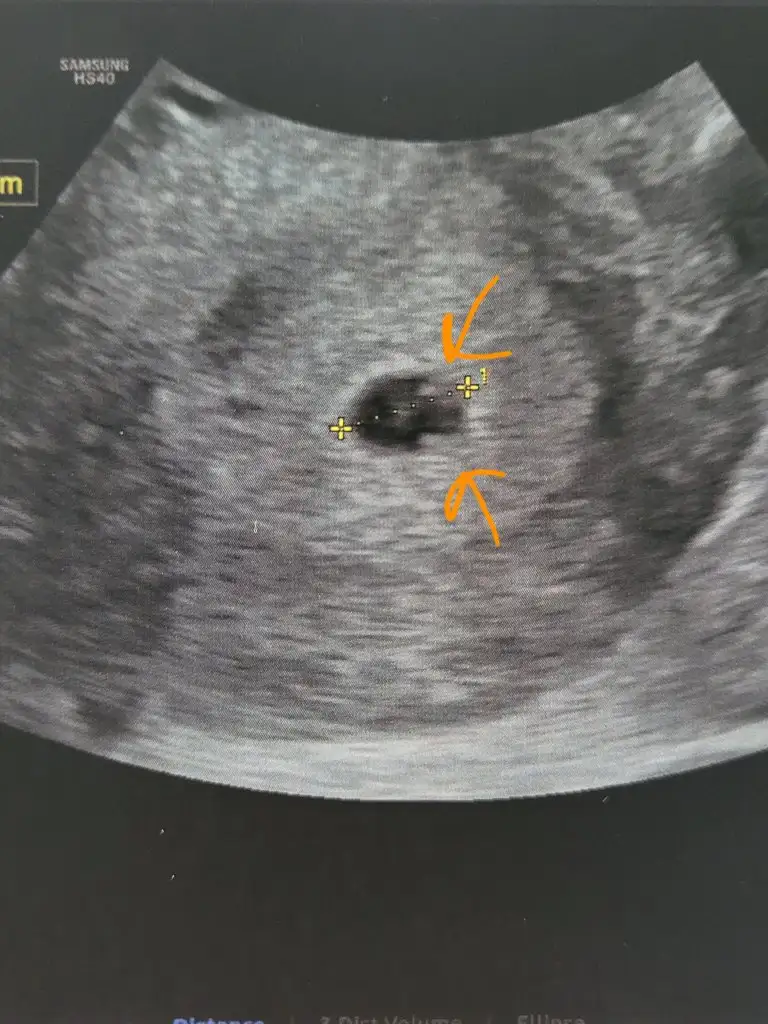

Ama sanki kesemde 2 tane yolk kesesi var gibi

Yoksa benim uydurmam mi bilemedim

Atsam bakabilir misiniz

Su isaretledigim noktaciklarMerak ettim

Ay bende merak ettim şimdiSu isaretledigim noktaciklar

Daha once kese incelememistim hic ama hep kesenin icinde bitane baloncuk gormustum rastladiklarimda da

Ben mi yanlis yorumluyorum diye sorayim dedim

Ya inşallah nasipAy bende merak ettim şimdibana sorarsan bencede iki tane görünüyor